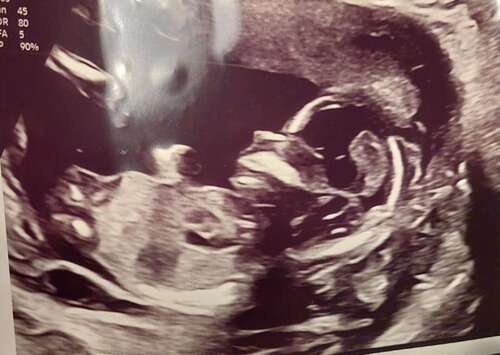

Is hier nog iets op te zien misschien 鈽猴笍? 13 + 1

En heb deze nog 馃き